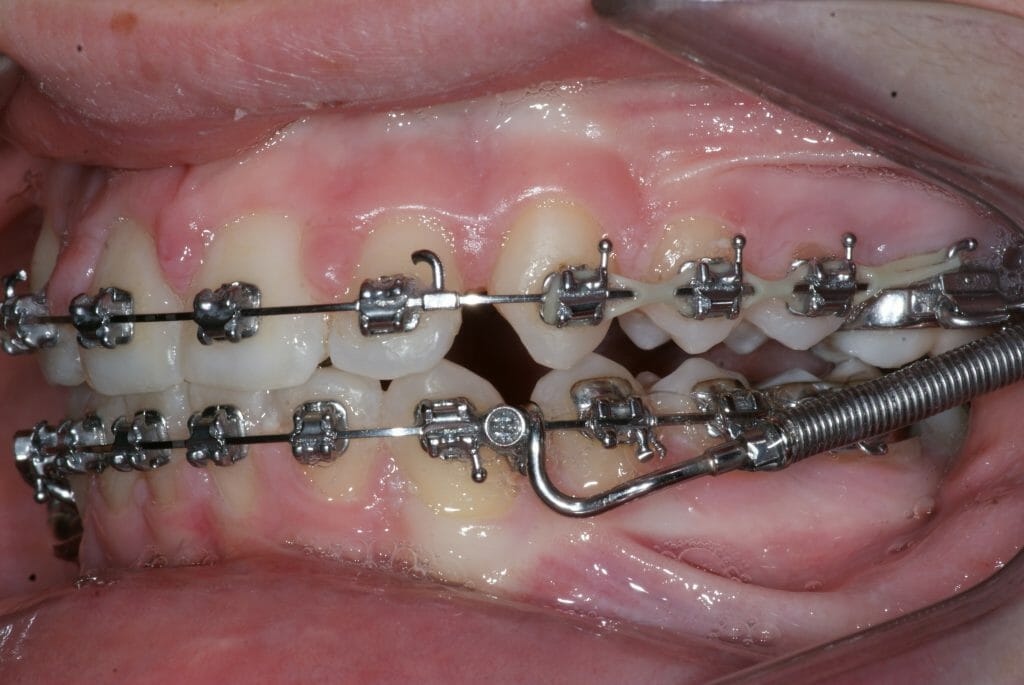

Appareil orthodontique Forsus© – 3M Unitek

Le Forsus© – 3M Unitek est un appareillage fixe muni d’un ressort installé chaque côté des fils et boîtiers (broches) afin de stimuler la croissance de la mâchoire inférieure.

Cet appareillage aide à déplacer les dents dans une position optimale tout en conservant la mâchoire inférieure vers l’avant. Cet appareil est utilisé chez les adolescents seulement.

Le Forsus© – 3M Unitek développe une force constante mais d’une intensité faible à modérée. Il est habituellement installé pour une durée de quatre à six mois (maximum). Il remplace le port des élastiques et réduit grandement la durée du traitement orthodontique par son efficacité. Une période de sept à dix jours est habituellement requise afin de s’adapter au Forsus. Il est tout à fait possible de bien manger et parler avec ce systeme de ressorts.

Les différentes vues de l’appareil orthodontique Forsus©